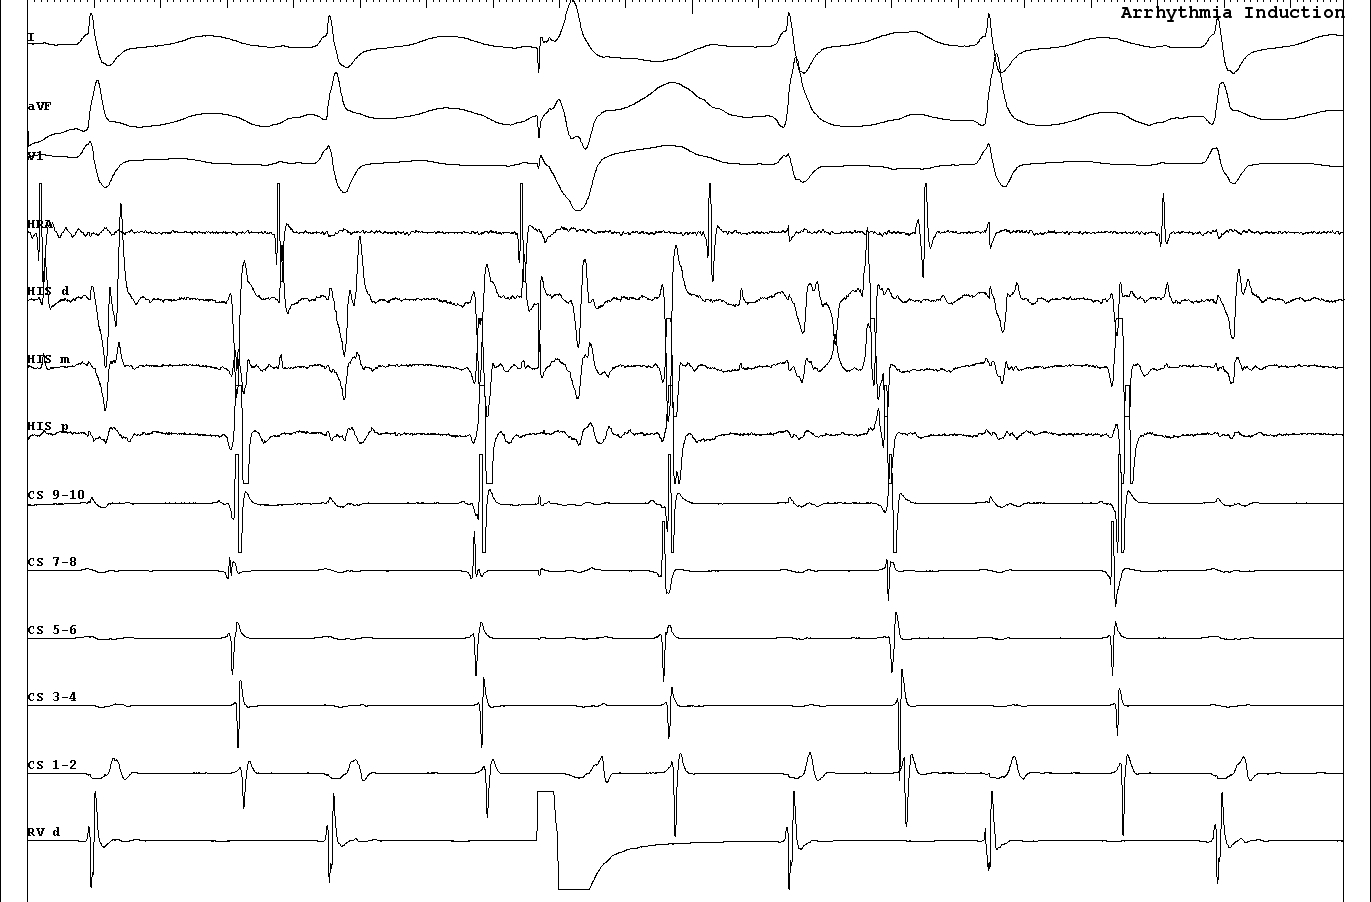

Termination during VOP - What now ?

vop_termination.jpg

Onset of VOP

vop_onset.jpg

Middle of VOP

02_constant and progressive fusion.JPG

Entrainment with antegrade His

entrain_with_fusion.jpg

Termination during VOP

termination_with_fusion.JPG